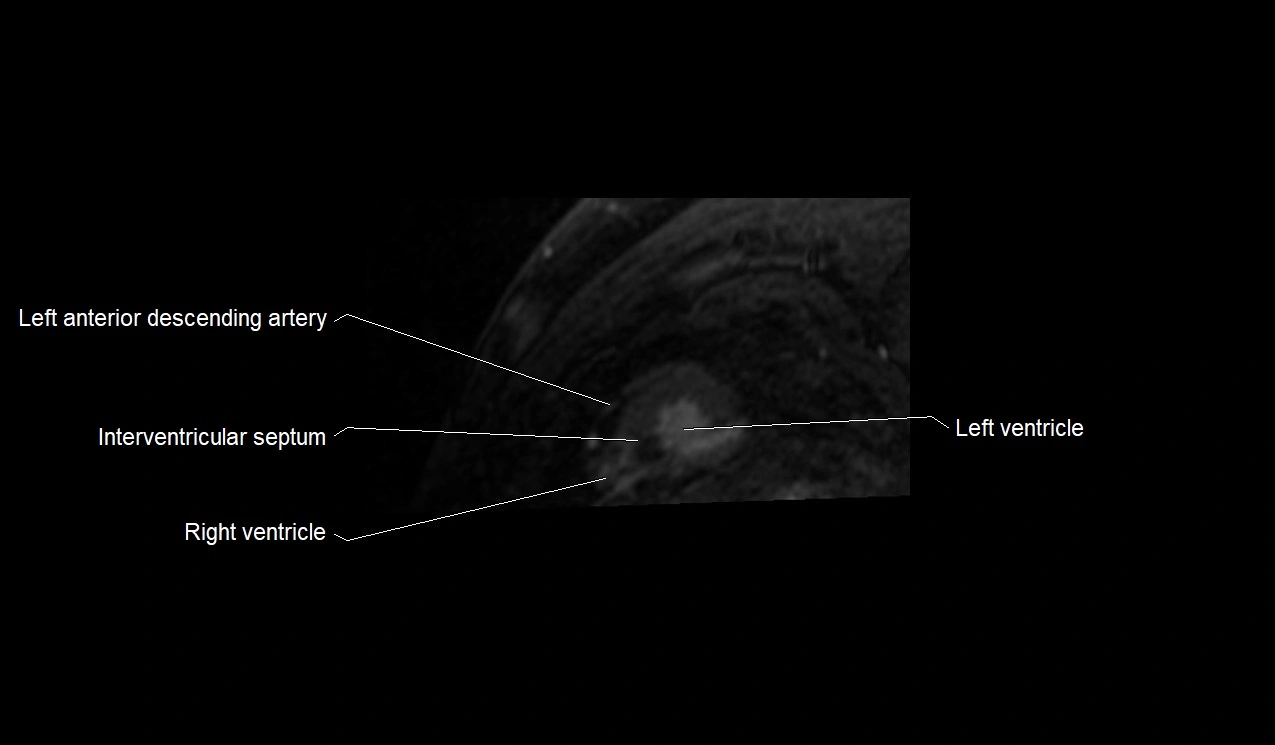

MRI image